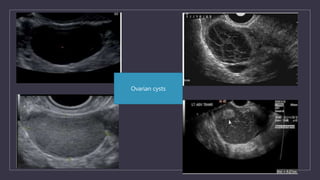

Ovarian cysts

IOTA SIMPLE USG RULES FOR OVARIAN MASSES